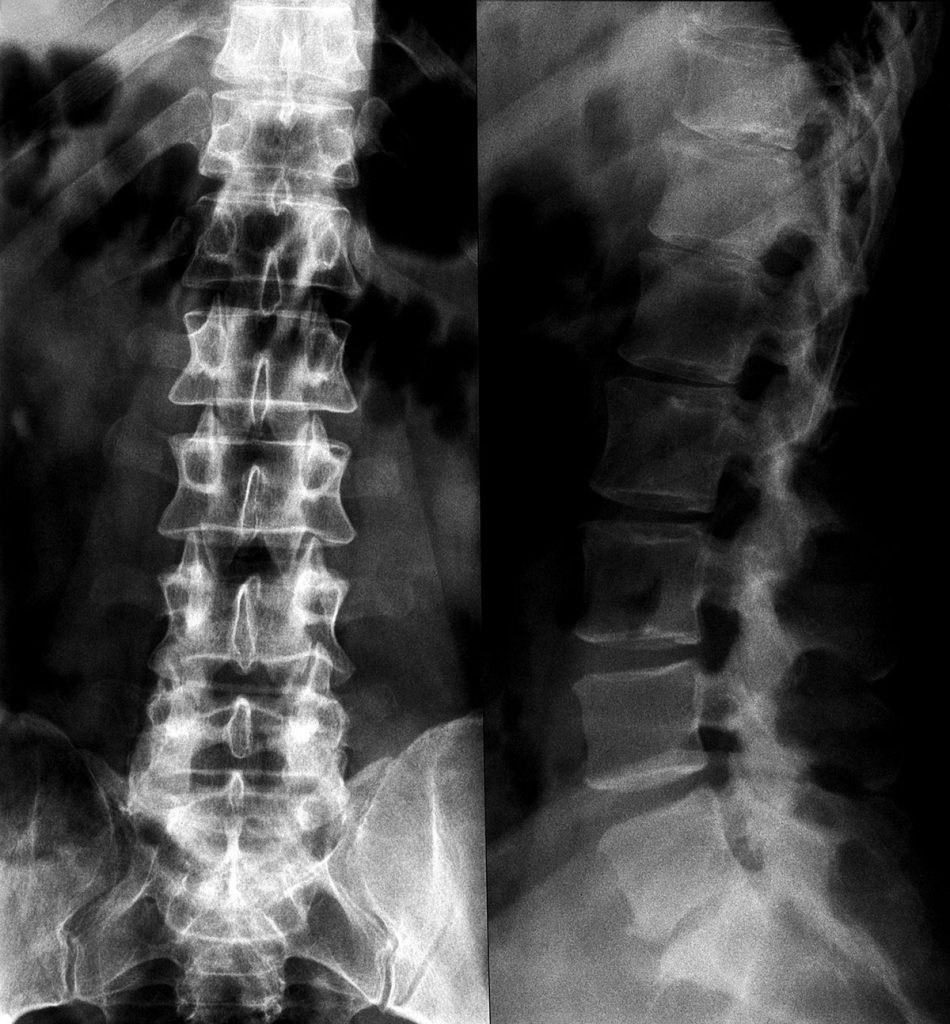

- تكمن مشكلة هشاشة العظام في ظهور الضغط على الأعصاب أو النخاع الشوكي ، بحسب عبد الغني ، الذي يوضح أنه مع الضغط على الأعصاب ، يعاني المرضى من أعراض مختلفة ، مثل: ب. شكاوى من الألم. يختلف الأمر باختلاف الأعصاب الأكثر ضغطًا والعمود الفقري يتحرك أكثر ، على سبيل

المثال قد يعاني البعض من آلام في الكعب والبعض الآخر قد يعاني من آلام في الركبة أو الفخذ.

- يشير أساتذة جراحة العظام والعمود الفقري إلى أن هذه الأعراض تشبه أمراض أخرى ، وبالتالي قد يتم تشخيص بعض الأشخاص بشكل خاطئ. لذلك ، من الضروري استشارة أخصائي للتأكد من التشخيص الدقيق للحالة.

- أفهم أن العرض الرئيسي لخشونة العمود الفقري هو صعوبة الاستقامة أو الشعور بألم شديد في الظهر ، ويرجع ذلك أساسًا إلى أن الخشونة تخلق نتوءات عظمية ويزيد الضغط على الأعصاب من الألم. يكون في الخلف ويمتد إلى أجزاء أخرى من الجسم ، مثل الساقين على وجه الخصوص ، وغالبًا ما يعاني المريض من تنميل في إحدى الساقين أو كلتيهما.